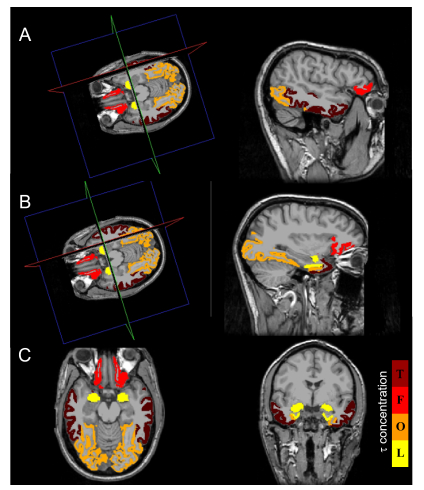

• Given the complexity, unknown causes, and lack of effective treatments for Alzheimer's disease (AD), mathematical modeling offers a valuable approach to its understanding. Models, once validated, offer a powerful tool to test medical hypotheses that are otherwise difficult to directly verify. Here, our focus is to elucidate the spread of misfolded $ \tau $ protein, a critical hallmark of AD alongside A$ \beta $ protein, while taking the synergistic interaction between the two proteins into account. We consider distinct modeling choices, all employing network frameworks for protein evolution, differentiated by their network architecture and diffusion operators. By carefully comparing these models against clinical $ \tau $ concentration data, gathered through advanced multimodal analysis techniques, we show that certain models replicate better the protein's dynamics. This investigation underscores a crucial insight: when modeling complex pathologies, the precision with which the mathematical framework is chosen is crucial, especially when validation against clinical data is considered decisive.